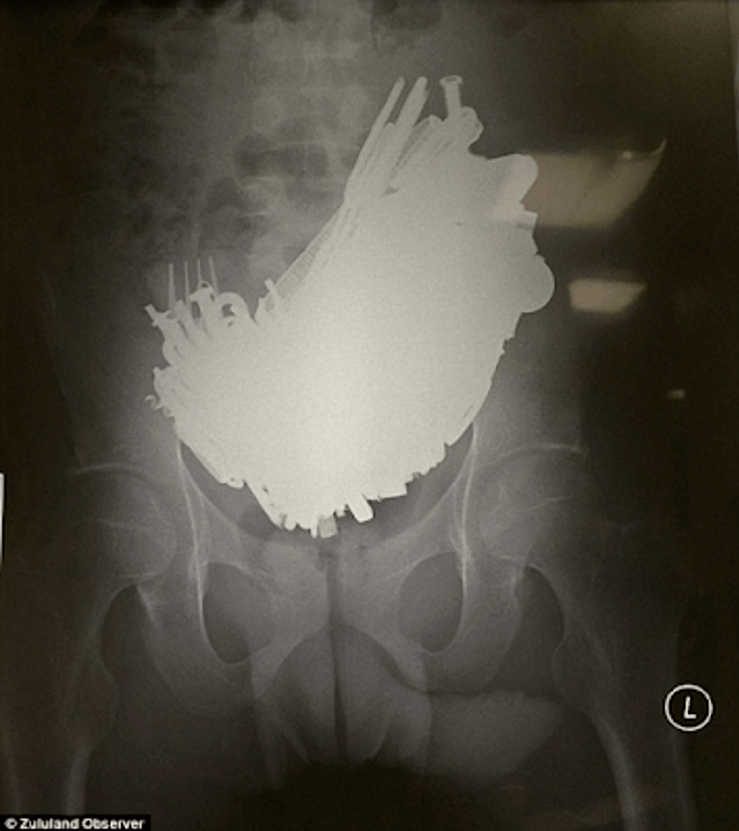

As explained by Mulder in the TV series The X -Files, ‘allotriophagy’ is defined in witchcraft lore as ‘the vomiting or disengorgement of strange or foul objects, usually associated with someone possessed by or obsessed with the Devil or other demons’. Current medical literature, however, uses the terms Allotriophagy, Pica, Cittosis, and Cissa interchangeably to describe a disorder in which the individual is compelled to eat non-nutritive substances such as clay, cloth, dirt, hair, paint chips, pebbles, ash, starch, ice, and even faeces, blood, and urine, with no aversion to actual food. The X-ray above is of the abdomen of a 48-year-old homeless man, and shows small foreign bodies scattered throughout the entire colon, and the X-ray below of a man who ingested 227 metal objects!

Abdominal X-Ray of a South African man who consumed 227 metal objects (weighing 4.5lbs) including a screwdriver!